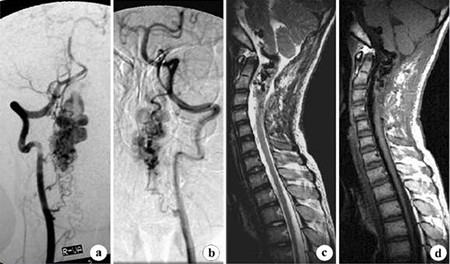

脊髓血管畸形是指脊髓血管先天发育异常形成的血管病变。它不包括脊髓血管母细胞瘤(血管网状细胞瘤)等血管性肿瘤。脊髓血管畸形占脊髓肿瘤的少部分。硬脊膜动、静脉瘘(AVF)患者中,大多数为男性,发病在40岁以上;而硬脊膜下血管畸形,男女有相似的发病率,10~30岁为发病高峰。

这些病变通常需要做专业检查诊断,对具有波动性症状的病人进行连续磁共振扫描,病变的体积可能有所变化,脊髓造影和血管造影很少有异常,通常不能做出海绵状血管畸形的诊断,有时有必要行脊髓血管造影,对海绵状血管畸形与其他类型的血管畸形区别。